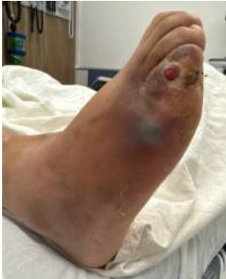

Vital signs include a blood pressure of 154/94 mmHg, heart rate of 130 beats/min, respiratory rate of 26 breaths/min, and temperature of 100.7°F (38.2°C). Physical exam shows a quarter-sized ulceration on the lateral aspect of the fifth digit on the dorsum of the right foot. There is green-blue discoloration noted proximal to the ulceration along the dorsal, lateral aspect of the fifth metatarsal. The left foot is status-post transmetatarsal amputation. There is also an amputation to the first digit on the right foot. Dorsalis pedis pulses are 2+ bilaterally. The foot motor exam is intact

Fig. 1. Ulceration and cutaneous color change to the dorsal, lateral aspect of the fifth digit on the right foot